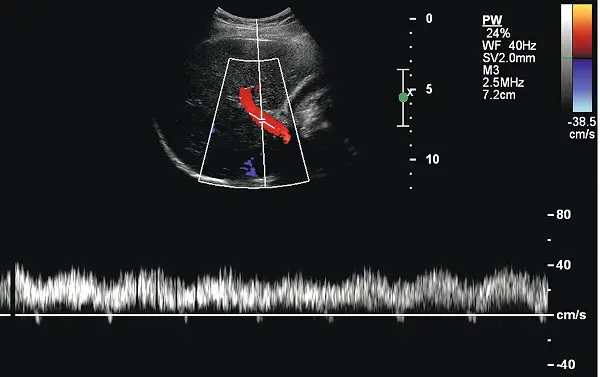

下圖為彩色都卜勒超音波影像,主要是量測那一條血管?

- 上半部影像(B-mode 與 Color Doppler):

- 顯示出肝臟實質構造,在彩色都卜勒的取樣框(Color box)中,可見一條相對粗大的血管,呈現紅色血流。

- 在預設的彩色對應圖中,紅色代表血流方向朝向探頭。在經由右側肋間或右側肋骨下掃描肝臟時,朝向肝臟內部的血流(向肝性血流,Hepatopetal flow)會朝向探頭,因此呈現紅色。

- 下半部影像(PW Doppler 脈衝波都卜勒):

- 頻譜顯示血流皆位於基線(Baseline, 0 cm/s)之上,證實為朝向探頭的正頻移。

- 波形呈現連續性(Continuous)、相對平緩的單相波(Monophasic waveform),僅受到呼吸或心跳影響而有輕微的起伏(gently undulating)。

- 觀察右側的流速標尺(Scale),血流速度大約落在 15~30 cm/s 之間,屬於中低流速的靜脈血流特徵。